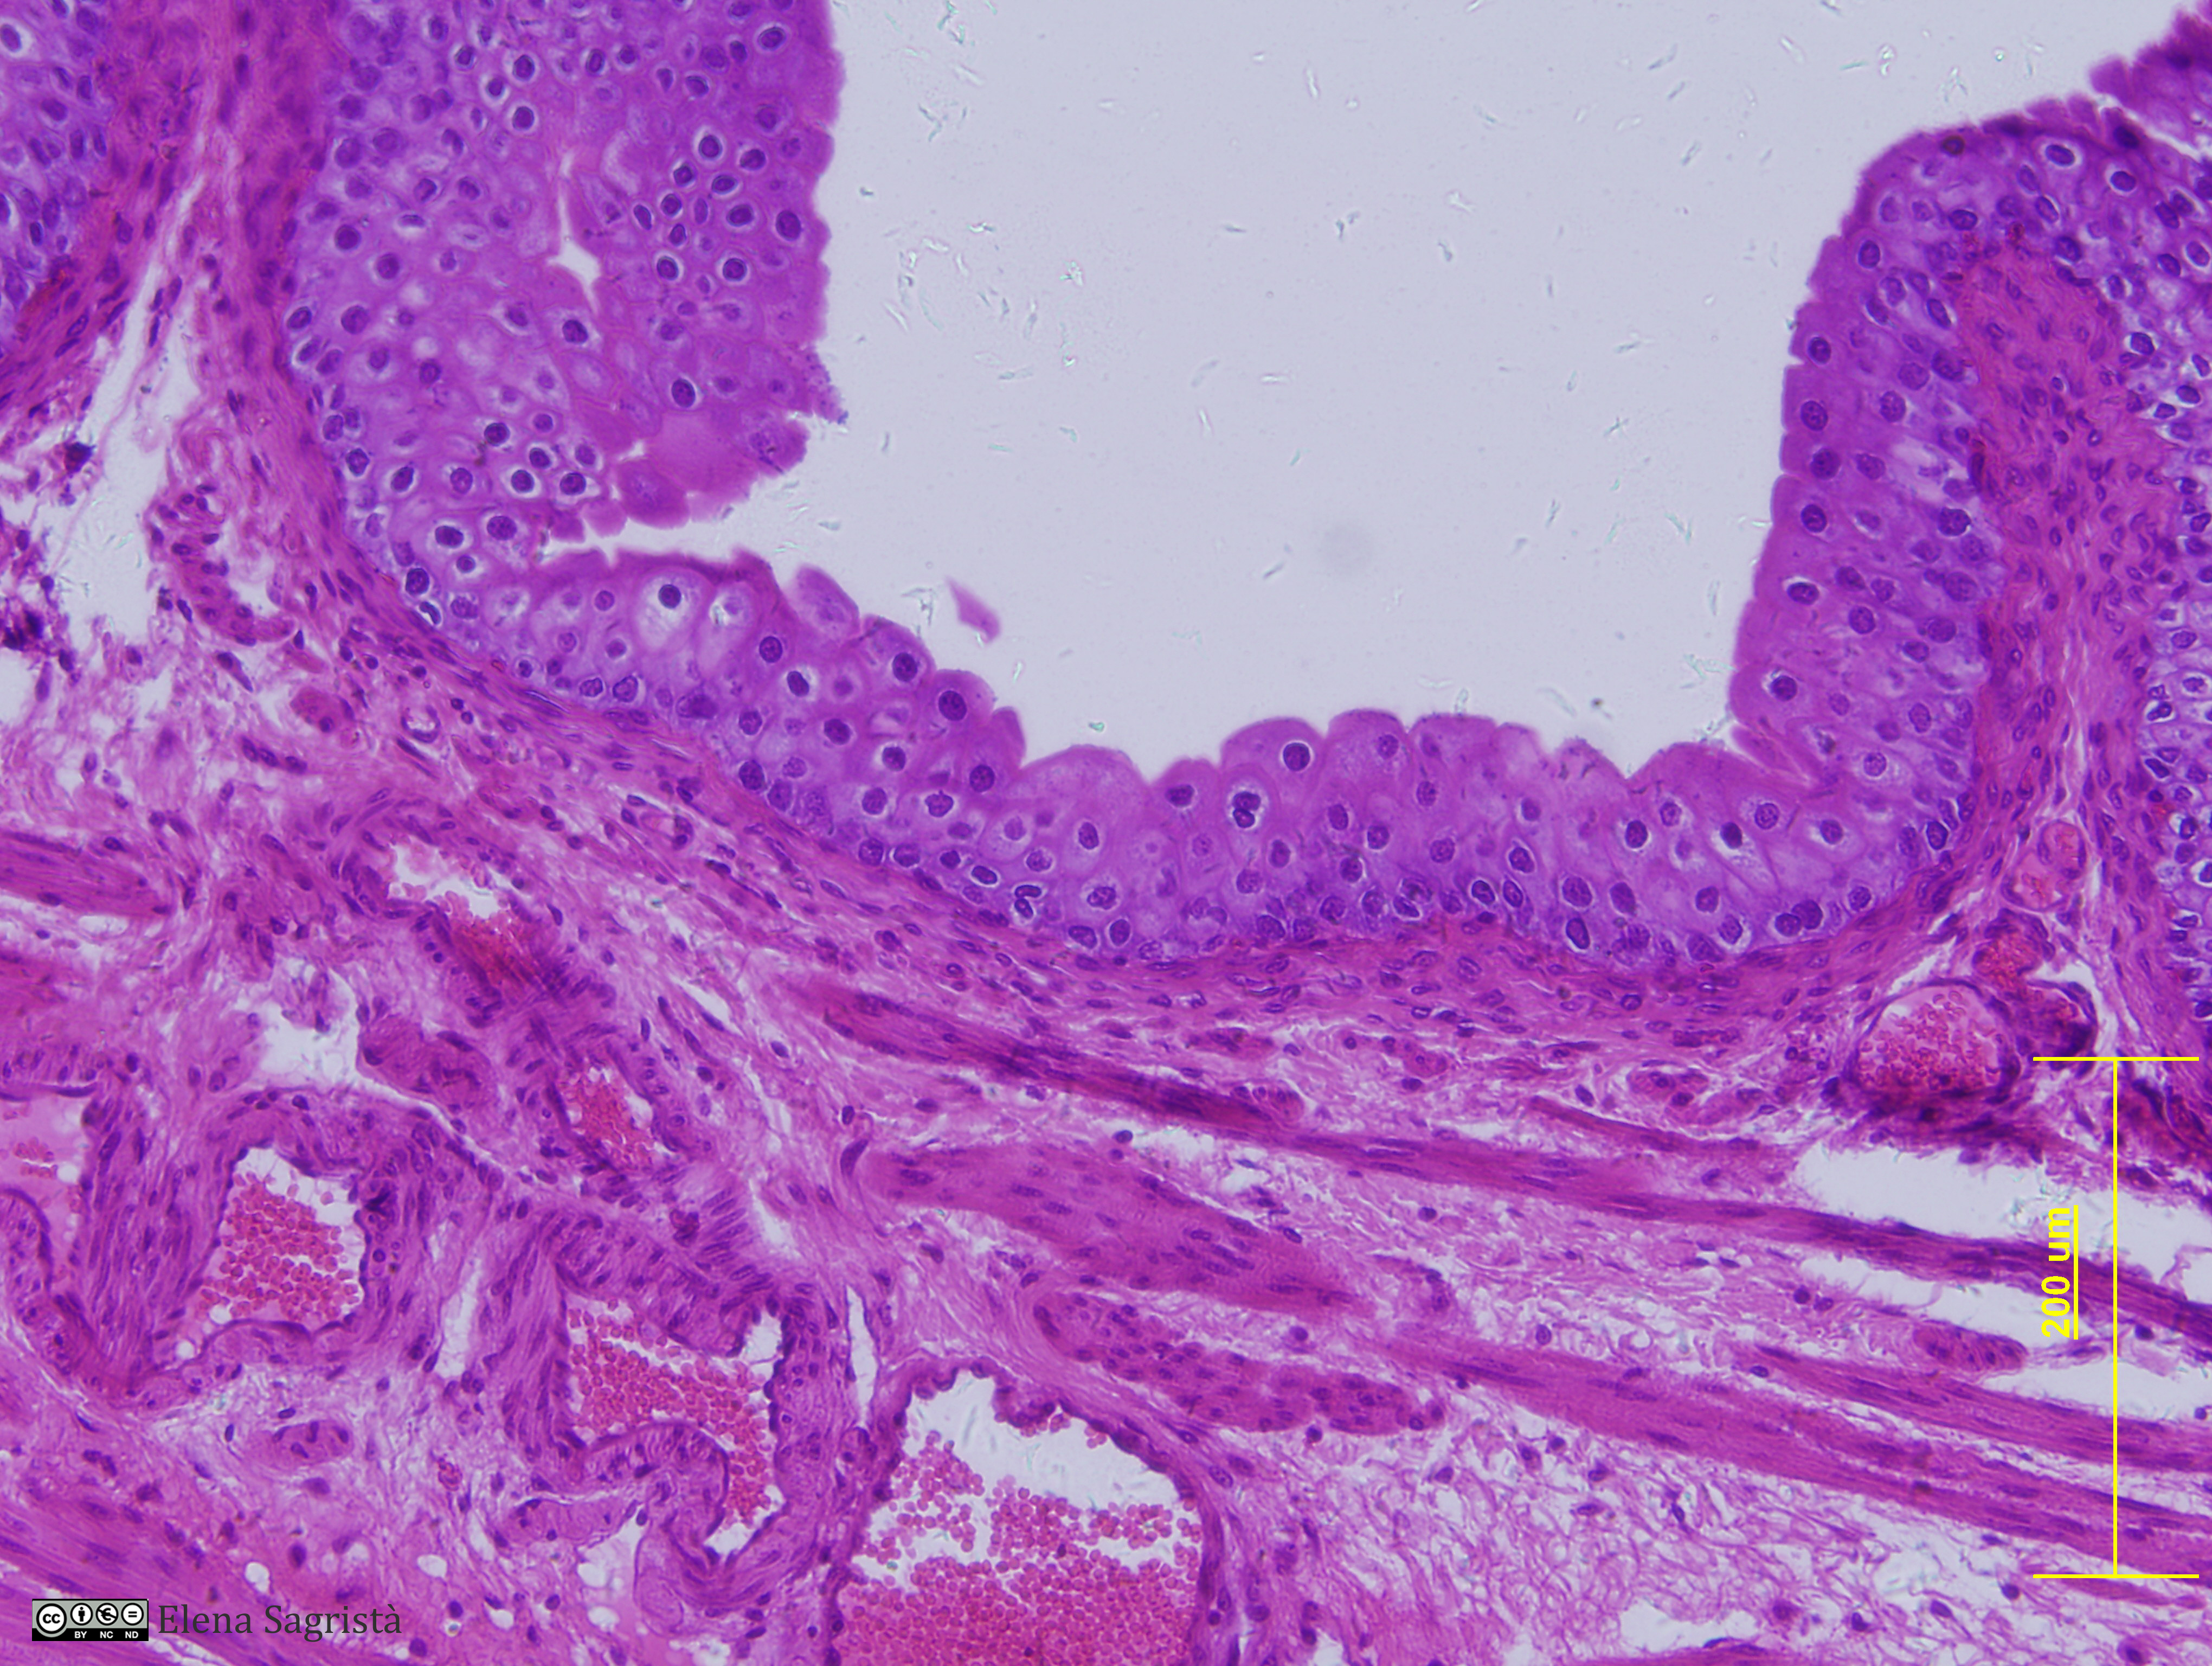

Histologia imatges: 21 Ronyò i Bufeta

Imatges de preparacions histològiques de Ronyò i Bufeta. Microscopia òptica.